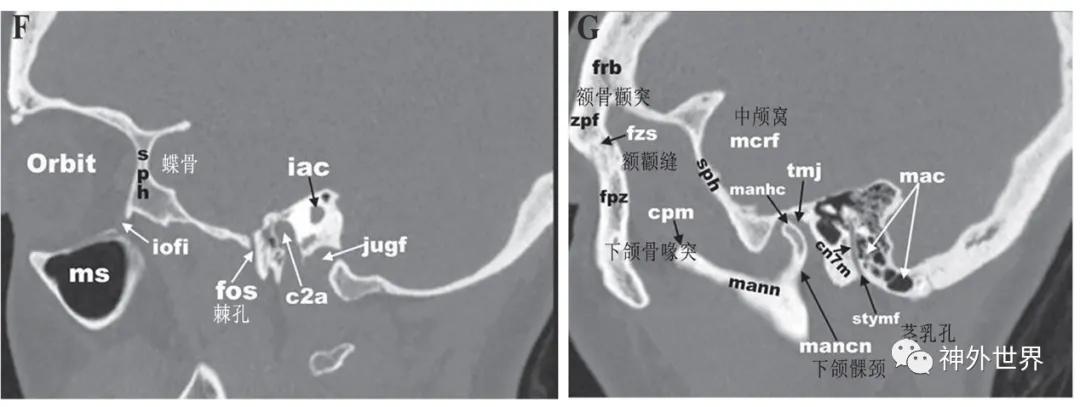

图4:颅底CT骨性冠状面影像解剖

图5:颅底CT骨性矢状面影像解剖